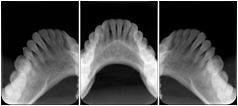

Cephalometric Series Structured Display

Figure OO-2. Cephalometric Series Structured Display

3. A dental provider wishes to capture a series of DICOM IO images for the patient’s dentition. The tooth morphology, teeth are divided into molars, premolars, canines and incisors, and a number of images for each jaw. The anatomic information was captured utilizing the triplet of schema. This standard code sequence is based on ISO 3950-2010, Dentistry - Designation system for teeth and areas of the oral cavity.

In most standard cases, images are oriented in structured layouts. These structured displays are useful to be shared between providers for reference purposes.

Table OO.1.1-1 shows structured display standard templates, where Viewset ID is based on the Japanese Society for Oral and Maxillofacial Radiology (JSOMR) classification provided by JIRA (Japan Medical Imaging and Radiological Systems Industries Association, www.jira-net.or.jp). Expected or typical teeth to be imaged location, region and designation codes are based on ISO 3950-2010, Dentistry - Designation system for teeth and areas of the oral cavity. For all the hanging protocols listed in OO.1.1-1, the value to use for Hanging Protocol Creator (0072,0008) is "JSOMR" and the value to use for Hanging Protocol Name (0072,0002) does not include "JSOMR" (e.g., "DL-S001A", not "JSOMR DL-S001A").